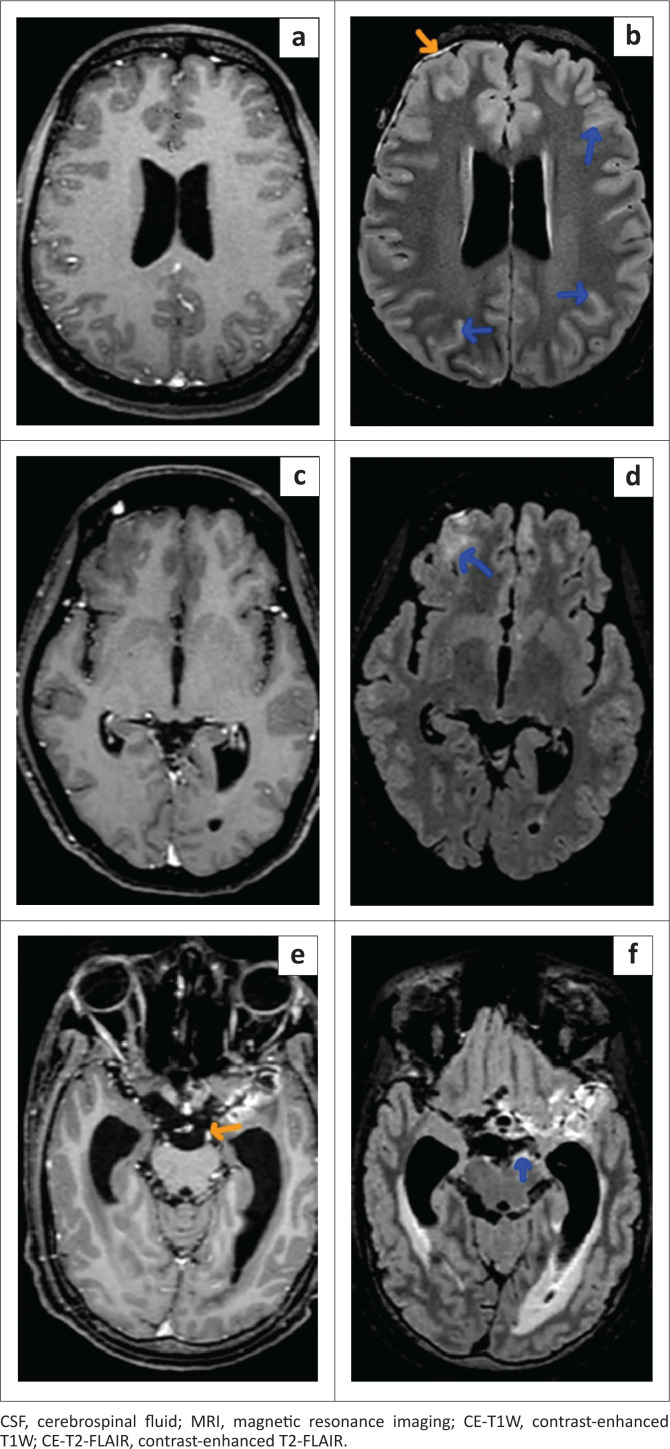

Background: The contrast-enhanced T2-FLAIR (CE-T2-FLAIR) sequence on MRI, through the suppression of CSF and vascular signals, can detect subtle meningeal enhancement in meningitis that may not be appreciable on the routinely used contrast-enhanced T1W (CE-T1W) sequence.

Method: A retrospective study was conducted on 53 patients with clinically suspected meningitis referred for brain MRI. Twenty-seven patients, positive for meningitis on CSF analysis, were classified as the case group; the remaining patients were designated as controls. The pre-contrast, CE-T1W and CE-T2-FLAIR images were assessed and analysed, qualitatively for the detection of abnormal meningeal enhancement, and quantitatively by measuring single pixel signal intensities (SPSI) over the meninges and vessels.

Results: Contrast-enhanced T2-FLAIR demonstrated significantly higher sensitivity (92.59% vs. 57.69%), negative predictive value (92.59% vs. 70.27%) and diagnostic accuracy (94.34% vs. 78.85%) compared to CE-T1W. Additionally, CE-T2-FLAIR showed significantly greater meningeal SPSI and enhancement than CE-T1W.

Conclusion: Contrast-enhanced T2-FLAIR is better at detecting abnormal meningeal enhancement in meningitis than CE-T1W, because of significantly greater signal intensity and enhancement of the meninges compared to vessels.